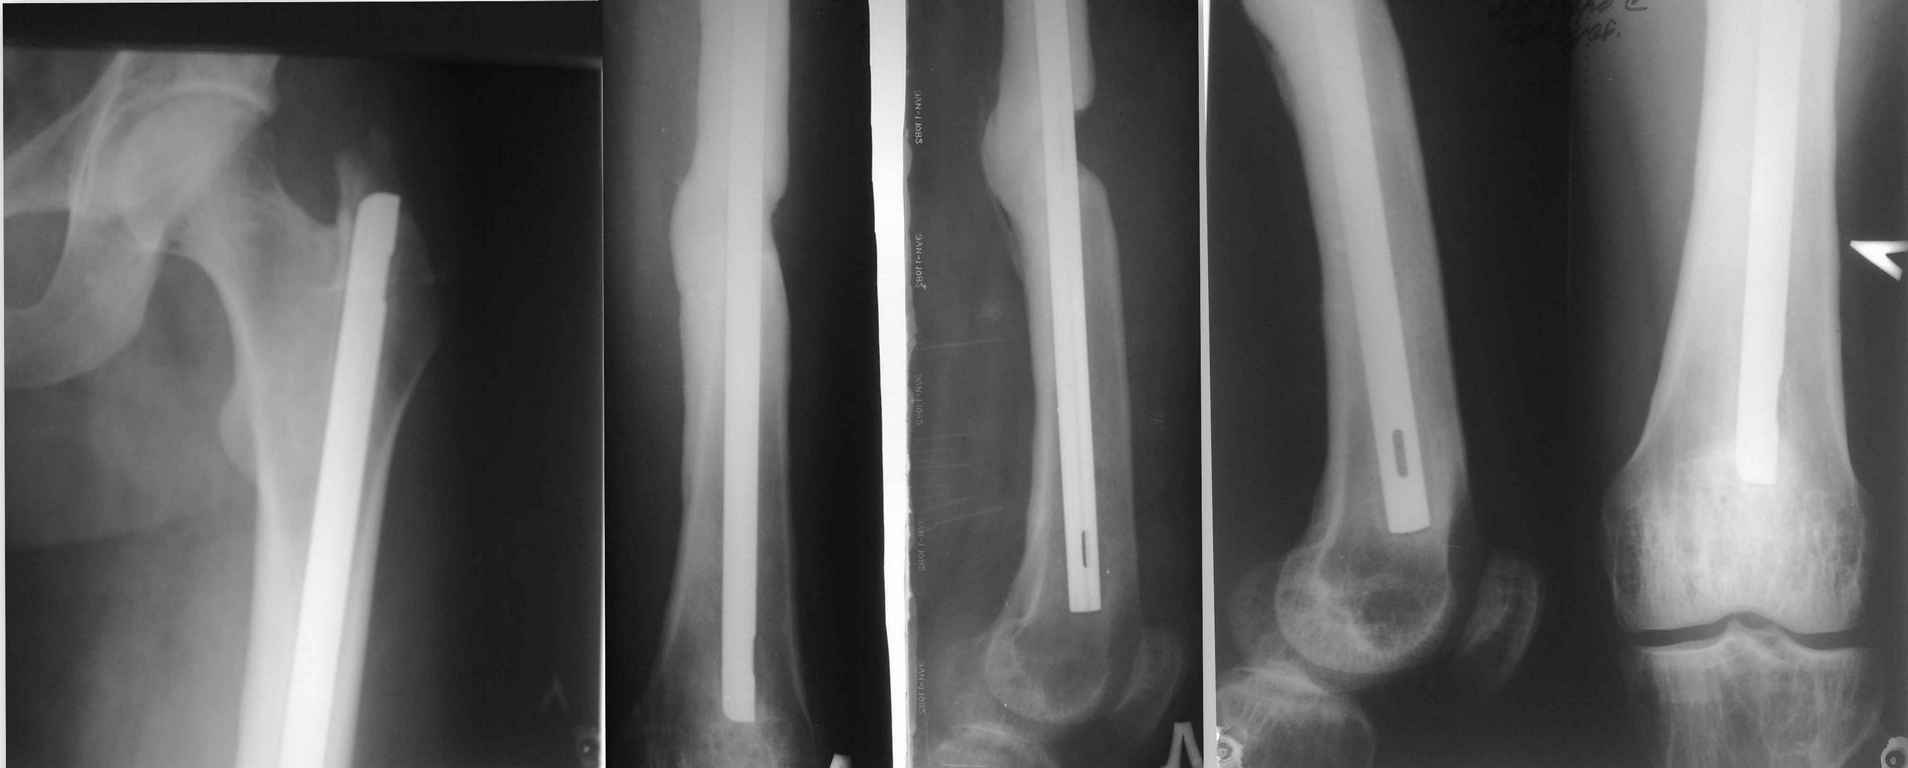

Здравствуйте Уважаемые коллеги! Просим совета. Есть больной 35 лет. Который получил

сочетанную травму в результате ДТП более 2х лет назад. Оперирован на бедре МОС бедра штифтом,

на голени накостной пластиной, которая через 2-3 мес. осложнилась развитием остеомиелита,

попал затем к нам. Мы удалили пластину с Б/б кости и фиксировали в ВЧКО. Длительно лечился у нас

с остеомиелитом б/б кости левой голени и по месту жительства, в общем, с голенью вроде всё в

порядке на данный момент свищей нет. Бедро, сделанное в местной больнице ранее, тоже не

беспокоило, но теперь начало, по снимкам бедра, сделанным ранее около года назад отмечается

миграция стержня в бедре до 1.5 см. и появился на снимке дефект кости в области перелома. Ранее

его не было. Кожных трофических нарушений нет. Металл не пальпируется. Больной настаивает

на удаление металла. Как быть с учётом дефекта кости: удалять полностью штифт, с костной

аутопластикой? БИОС?